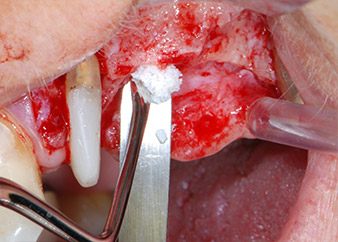

Vor der Insertion der Implantate und nach Überprüfung der intakten Schneiderschen Membran (Abb.9) wurde der interne Sinusboden an beiden Implantatpositionen mittels eines xenogenen Knochenersatzmaterials (Abb. 10) augmentiert.

CPITN-Sonde

Abb. 10: Einbringen von xenogenem Knochenersatzmaterial zur internen Sinusaugmentation: Das Material wird mit der CPITN-Sonde vorsichtig in apikaler Richtung komprimiert (nicht abgebildet).